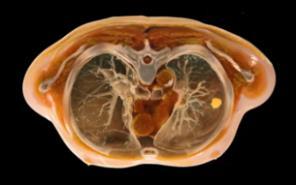

What if we could create a digital twin of the patient’s heart?

• Multiscale, Personalized Physiological Model of the patient’s heart

• Anatomy, Electrophysiology, Biomechanics (muscle contraction ), Circulation (ejection fraction, pressure dynamics)

• Mechanistic and statistical modeling

• Model is under our control

• Potential to test and prescribe best therapy for the patient – e.g., Cardiac Resynchronization Therapy

Ventricular Tachycardia Atrial Fibrillation Dyssynchrony – Heart Failure

Identify the ablation targets that will effectively terminate persistence AF? Identify the minimal ablation targets (catheter, RT) that will effectively terminate VT?

Cardiac radioablation –focus radiation using localization of VT exit

Anticipate the effects of CRT on patient’s cardiac function from preoperative data?